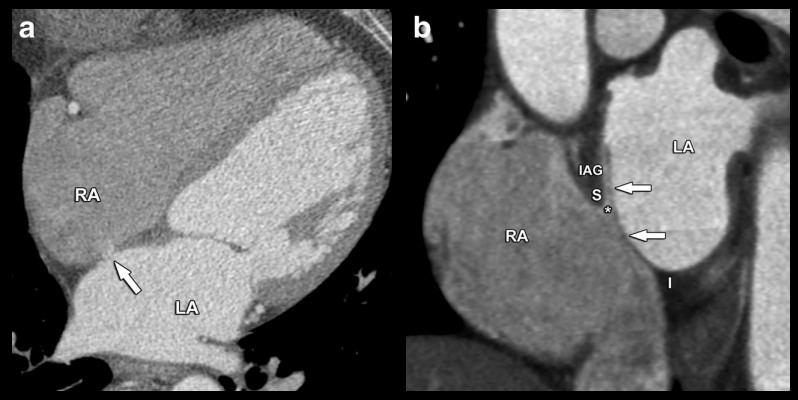

Foramen Ovale Perméable (FOP)

- Fuite de contraste entre OG → OD

- On peut voir la valve formée par le septum primum résiduel

- TTT: Double ombrelle (Amplatzer®)

Anévrisume du septum

- Protrusion de >10mm

- Dans le sens droit ou dans le sens gauche